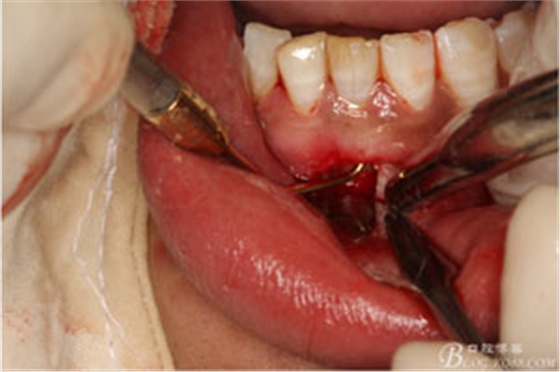

圖7.局部麻醉下,行下前牙唇側(cè)弧形切口,翻瓣可見31唇側(cè)骨壁有缺損,并有根充物暴露